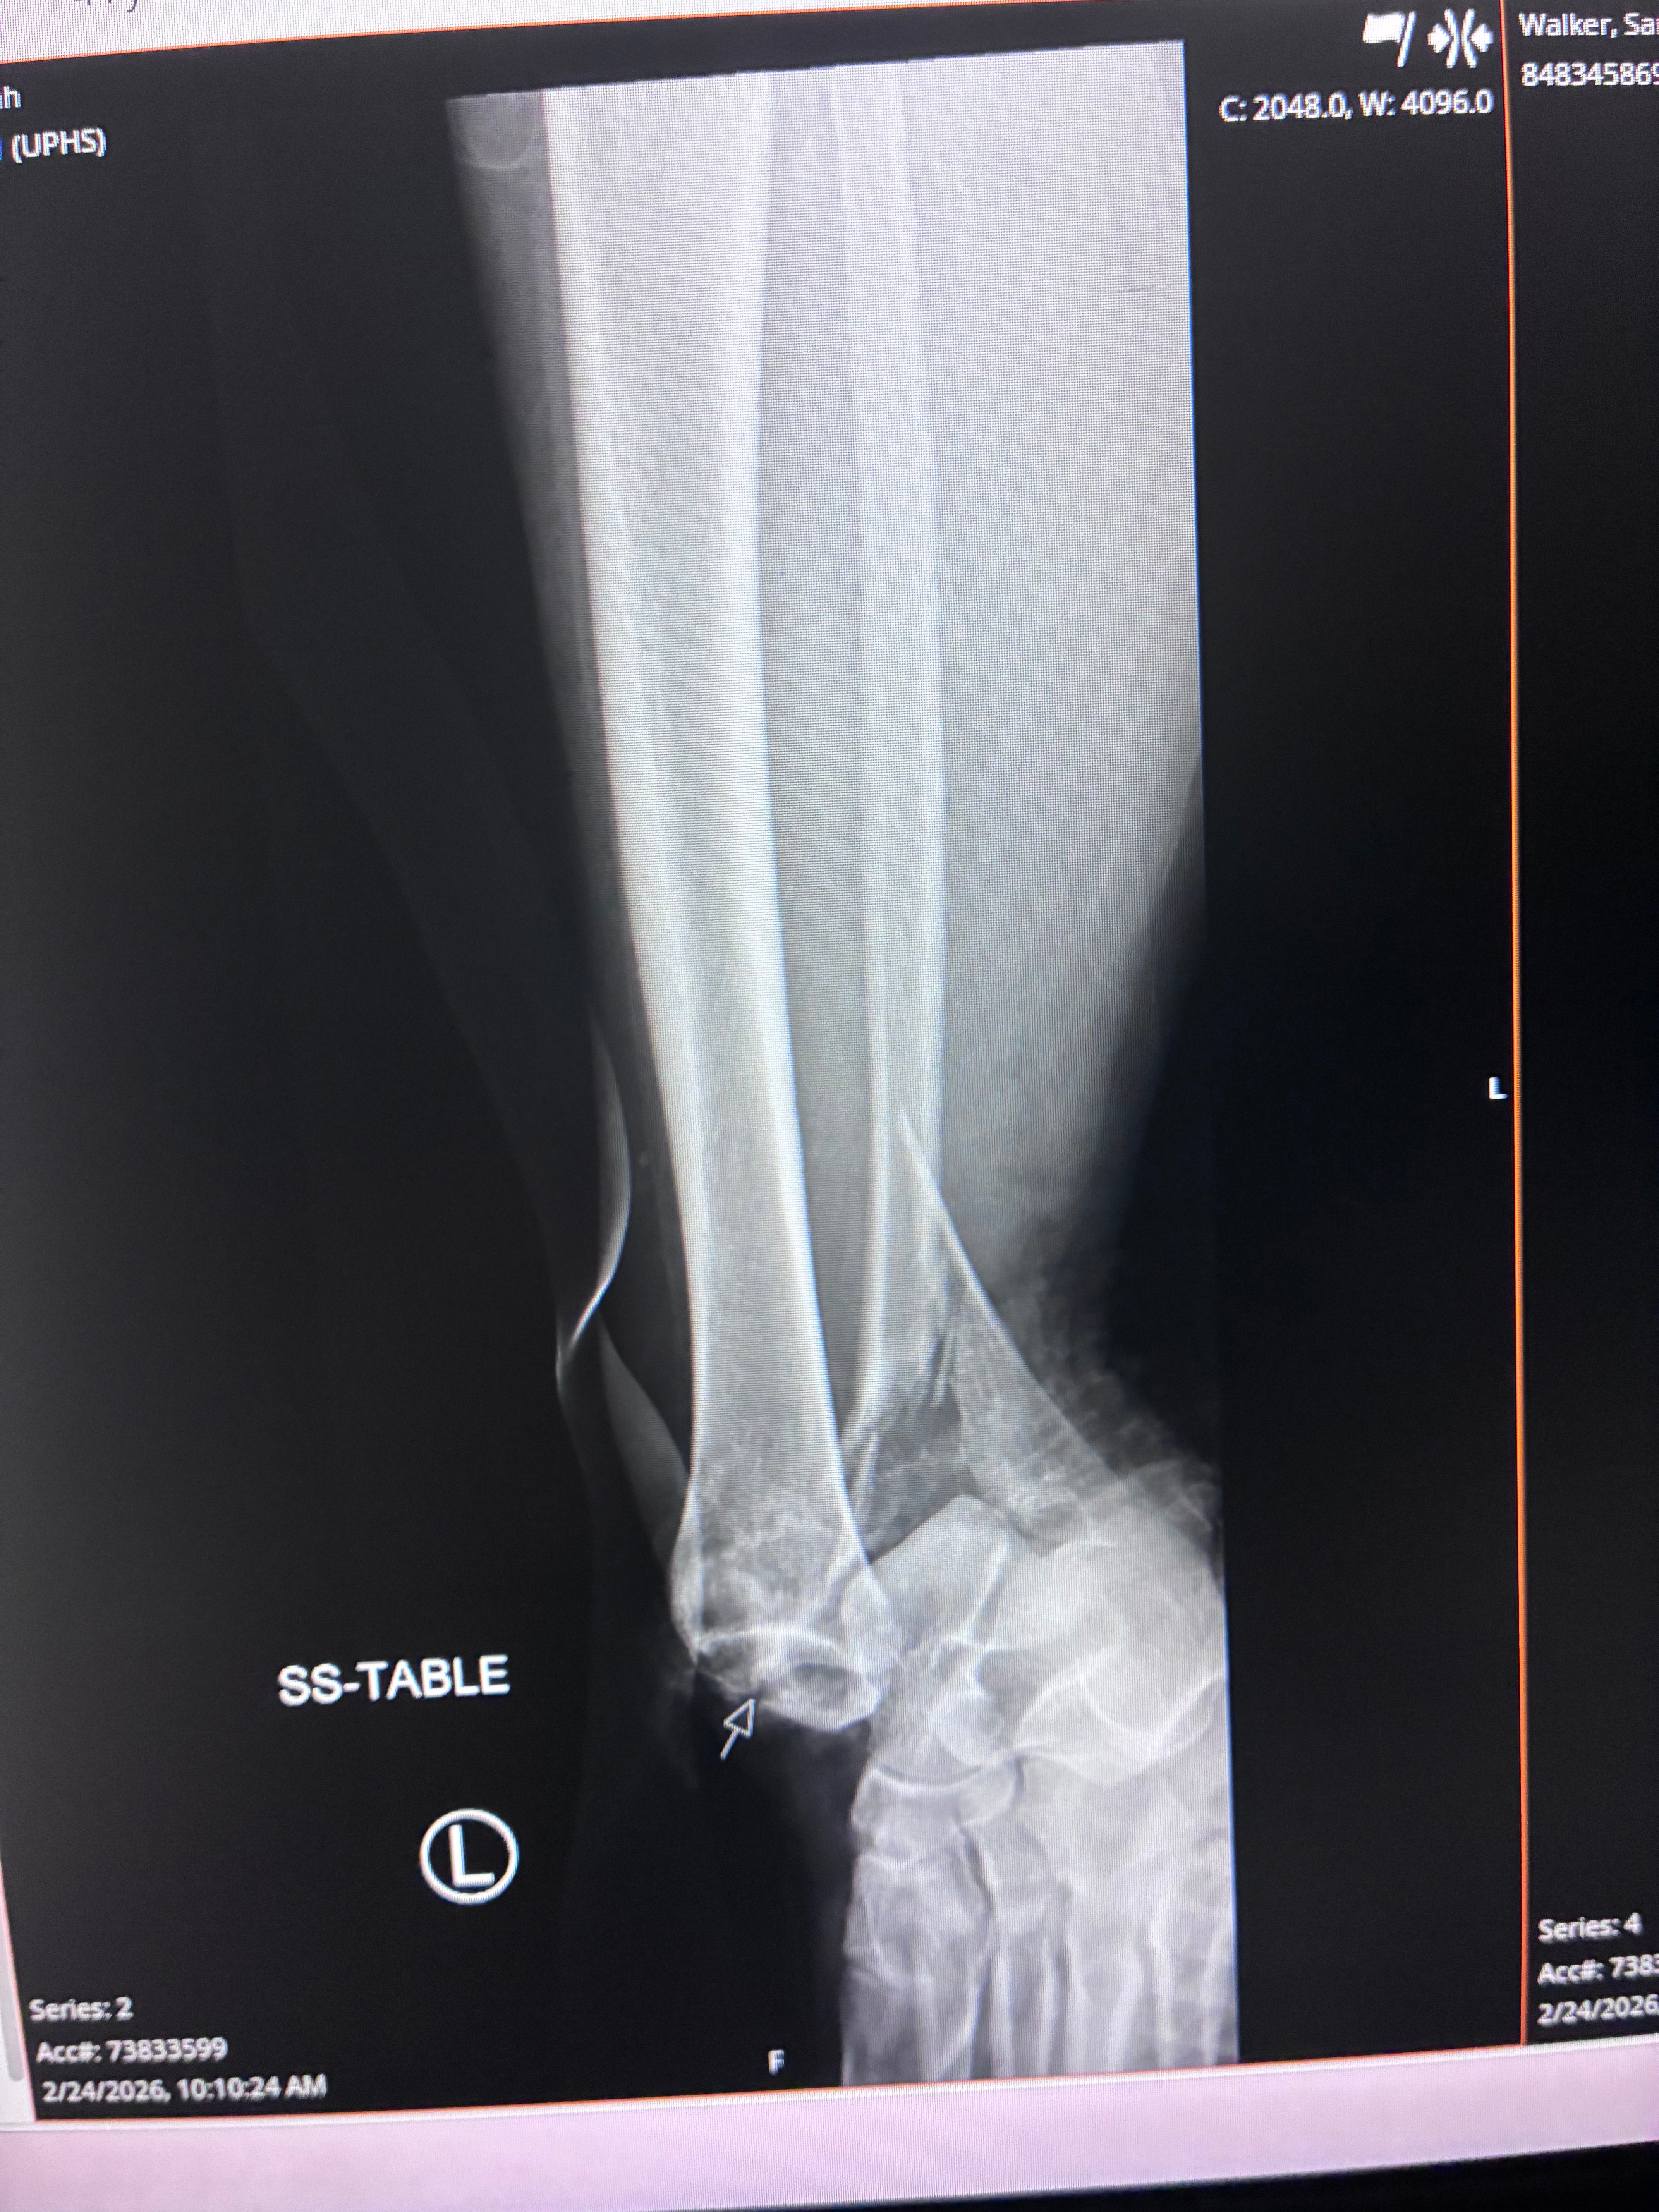

Hello, my name's Sarah, and on 2/24 I sustained a terrible injury. I slipped on ice and fell, which led to a compound fracture in my ankle and lower leg. My 10-year-old daughter placed the call to 911, while my 17-year-old daughter applied a tourniquet to my lower leg to stop the bleeding. I was rushed to the hospital where I underwent an emergency surgery to stop the bleeding and realign my bones. I've now received 2 surgeries, and I am currently recovering at home. I am unable to apply any weight to my leg, which means bed rest.